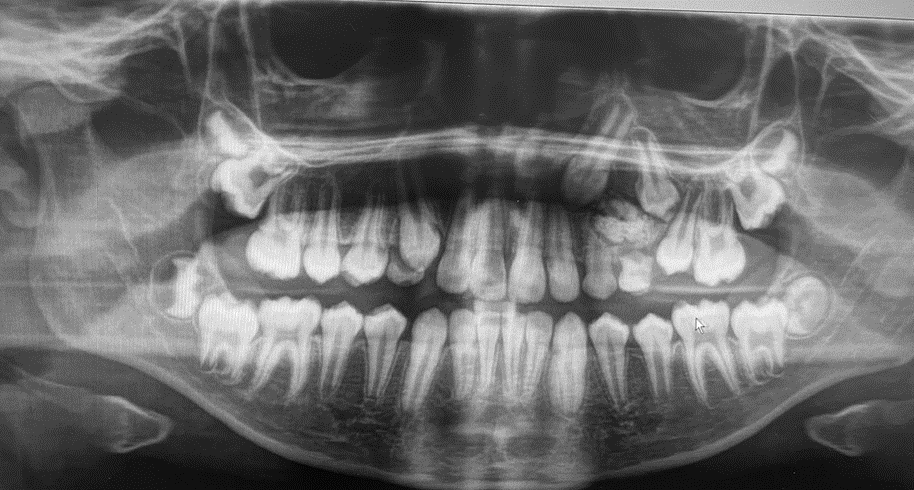

8-year-old boy with unusually shaped incisors and missing teeth

An 8-year-old boy was referred to a pediatric dentist because of the unusual shape of his mandibular incisors and several missing teeth.